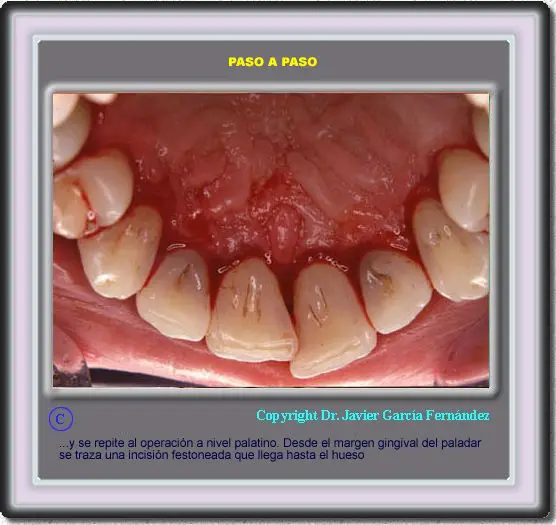

image11